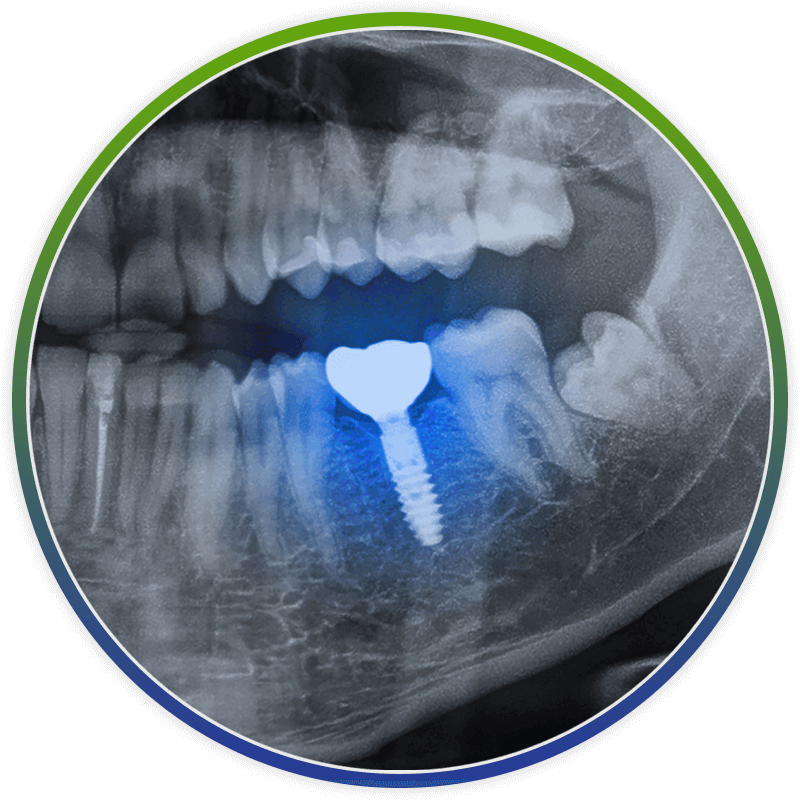

close up of dental implant xray

The most common approach to addressing failing dental implants is to completely replace them, a decision made following thorough evaluation and X-rays. When nonsurgical or surgical interventions like peri-implantitis treatment and bone grafts have not resolved the issue, total replacement typically offers the best outcome for your health and dental function.

Two main techniques exist for removing a failing dental implant from the bone. One method involves carefully cutting a small section of bone around the implant using tools like a piezo-electric device for precise removal. Alternatively, the implant can be gently “reverse torqued” out of the bone. In both cases, our priority is to preserve as much natural bone as possible to ensure more predictable and successful implant placement in the future.